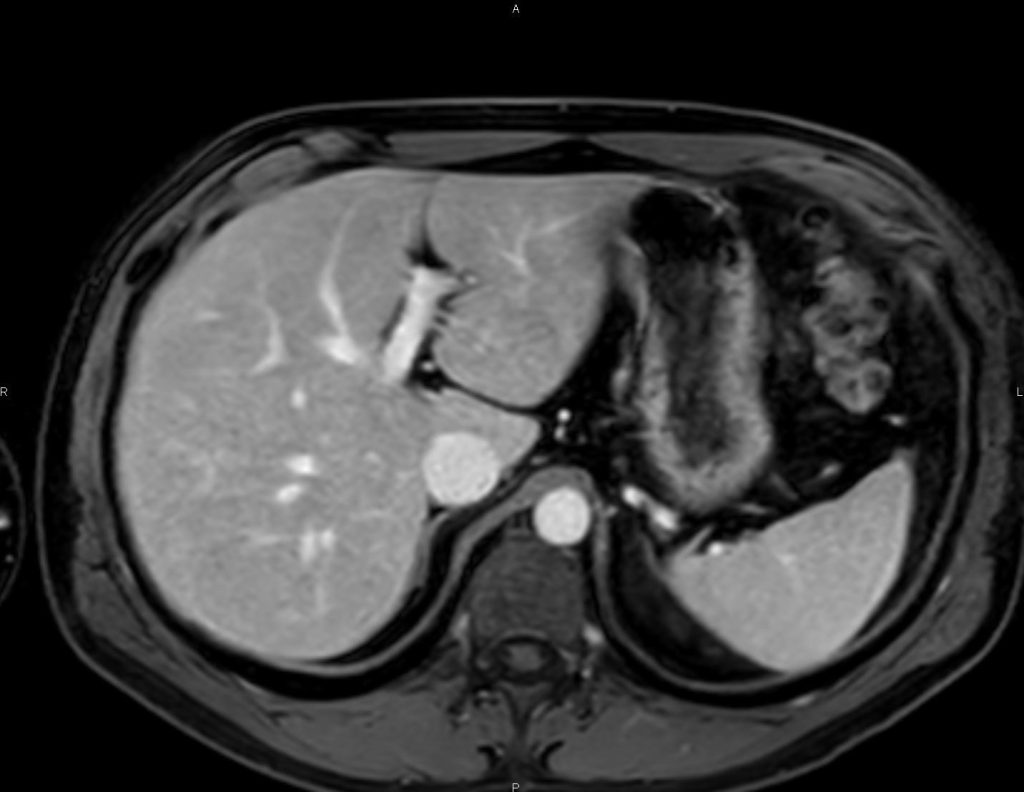

L’IRM abdominale est d’une grande utilité lorsqu’une analyse très fine des organes situés au sein de la cavité abdominale est nécessaire et que certaines lésions ne sont pas visibles avec les autres techniques d’imagerie (radiographie, échographie ou scanner).

Elle permet de réaliser des images en coupe ou acquisitions 3D apportant non seulement des informations sur l’anatomie de l’organe mais également sur la viabilité de certaines lésions et d’évaluer ainsi la réponse au traitement de façon plus précise.

Ce type d’exploration s’intéresse au foie, aux surrénales, aux reins, au pancréas, à la rate et au péritoine

Quelques exemples :

– recherche d’une surcharge en fer du foie,

– quantification d’une stéatose, suivi des fibroses intra-hépatiques,

– cartographie des lésions cancéreuses et suivi de leur réponse sous traitement,

– recherche de calculs au sein des voies biliaires ou de la vésicule.